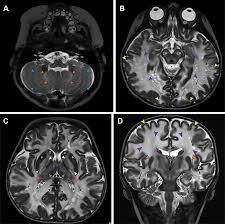

MRI imaging at 1, 3, and 6 months post-treatment shows progressive myelin growth following gene therapy.